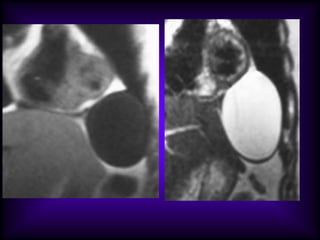

Mediastinal Cysts

The CT features of benign

mediastinal cyst are

(a) a smooth, oval or tubular mass with a well-

defined thin wall that usually enhances after

intravascular administration of contrast

material,

(b) homogeneous attenuation, usually in the

range of water attenuation (0–20 HU),

(c) no enhancement of cyst contents, and

(d) no infiltration of adjacent mediastinal

structures.

Cysts that contain serous fluid typically have

long T1 and T2 relaxation values, which

produce low signal intensity on T1-weighted

MR images and high signal intensity on T2-

weighted images.

Because cysts containing nonserous

fluid can have high attenuation at CT,

they may be mistaken for solid

lesions. MR imaging can be useful in

showing the cystic nature of these

masses because these cysts continue

to have characteristically high signal

intensity when imaged with T2-

weighted sequences regardless of the

nature of the cyst contents